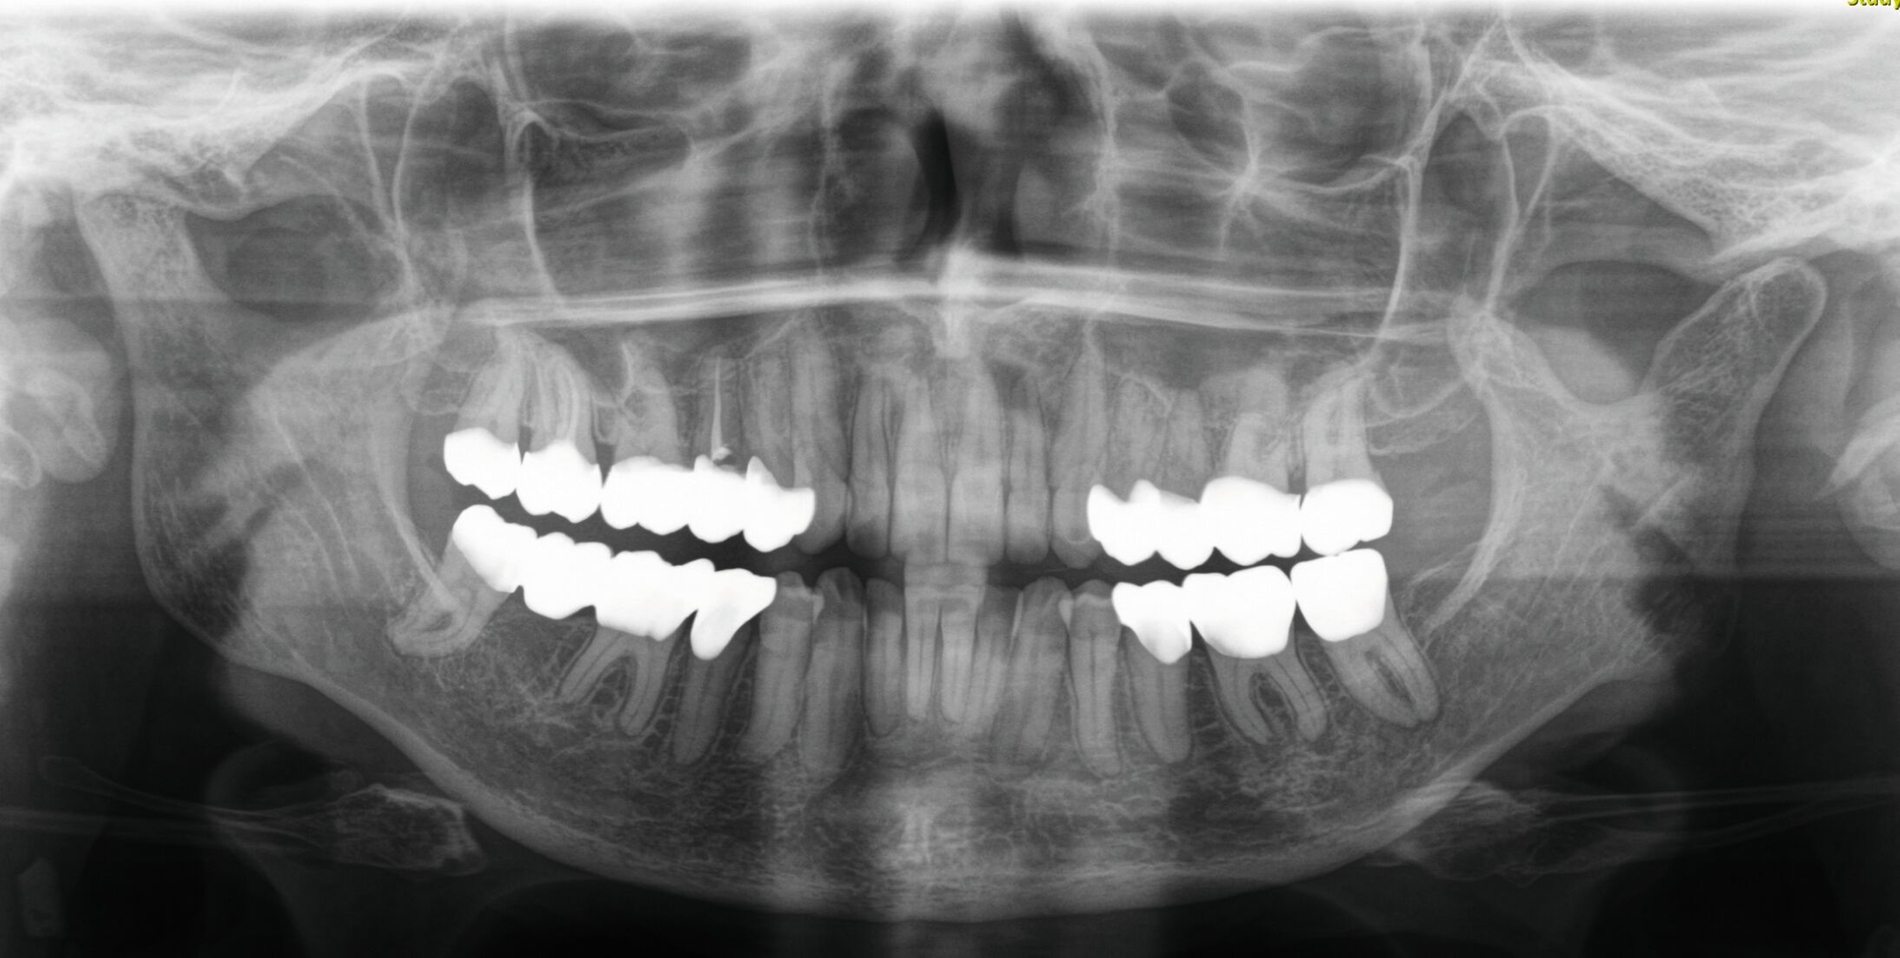

Im Rahmen der Konsultation der Mund-, Kiefer- und Gesichtschirurgie und der Kieferorthopädie erfolgte eine erneute radiologische Bildgebung (Abbildung 4). Die Patientin wurde im Anschluss beraten, dass eine Re-Osteotomie des ehemals frakturierten und nun in Fehlstellung verheilten Collumsegments links ihr Okklusionsproblem adäquat lösen könnte. Ebenso sei eine orthognathe Umstellungsosteotomie möglich. Nach ausführlicher Aufklärung entschied sich die Patientin allerdings gegen eine chirurgisch-kieferorthopädische und für eine rein prothetische Lösung. Die Patientin hatte derart Angst vor einem erneuten chirurgischen Eingriff, dass sie selbst die Aussicht auf eine längere und invasivere prothetische Behandlungsphase nicht abschreckte.

Die anschließenden Verlaufskontrollen zeigten klinisch stabile Verhältnisse. Der prothetische Behandlungsaufwand betrug etwa acht Monate inklusive Planung, Begutachtung, Durchführung und Inkorporation des Zahnersatzes. In den Folgeterminen wurde der Patientin noch eine Aufbissschiene für den Unterkiefer eingegliedert, um Schäden durch etwaigen Schlafbruxismus vorzubeugen [Macedo et al., 2007]. Für die Nachsorge empfiehlt sich ein halbjährliches Kontrollintervall. Die erfolgte Okklusionskorrektur im Seitenzahnbereich wird in Abbildung 11 deutlich.